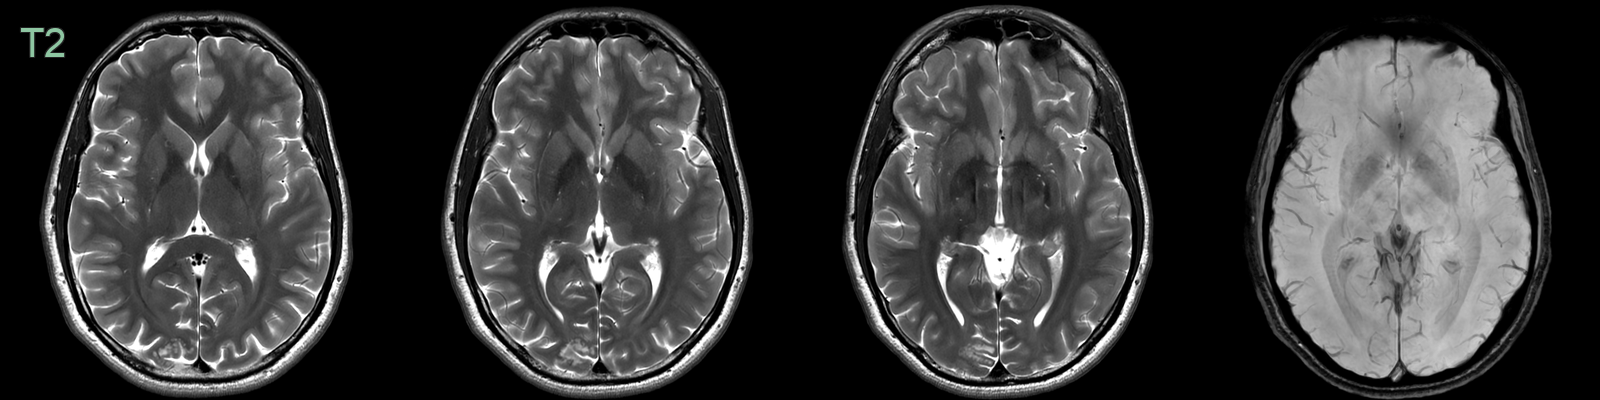

• Clustered subcortical hyperintensities in the right occipital pole were identified incidentally.

• The appearance, lack of enhancement and stability over four years, were consistent with MVNT.